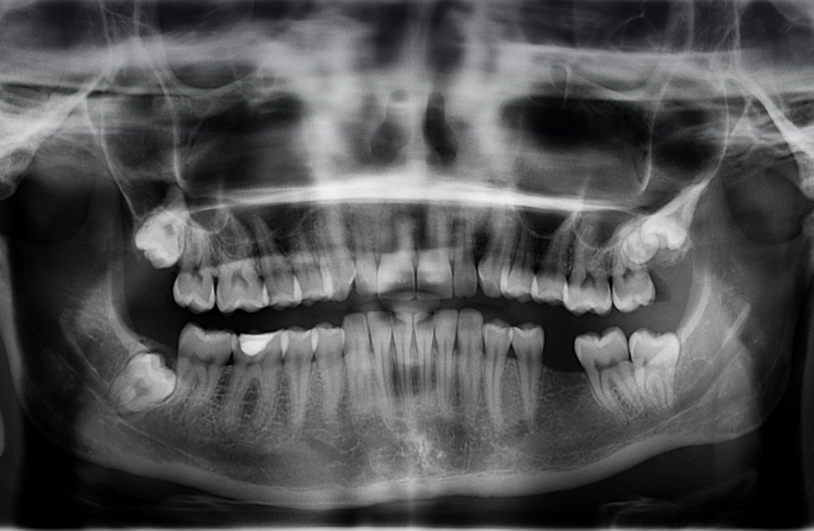

사랑니는 정상적으로 자라는 경우 무조건 발치할 필요는 없으나, 비정상적으로 자라 잇몸 아래에 충격을 가하면 칫솔이 닿기 어려워 충치가 쉽게 생겨날 수 있습니다. 잇몸의 일부가 밀려나 감염이 생기기 쉽기 때문이지만, 무조건적인 발치를 권하지 않습니다. 하지만 나이가 들수록 문제가 생기는 경우가 많이 있기는 합니다.